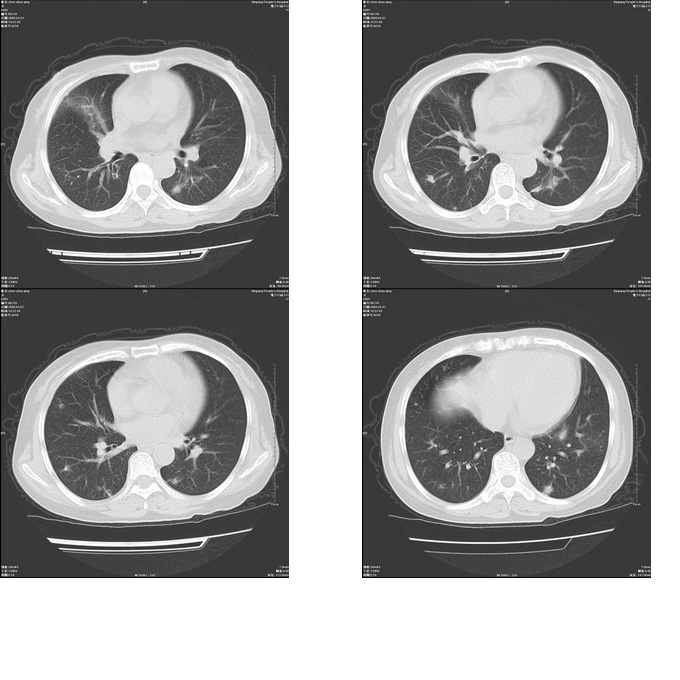

患者,女,48岁,发热伴陈发性咳嗽5天,偶尔痰中带血。体温约38°~40°;白细胞明显减低0.85x10的9次方/升。入院后抗炎、抗痨一周复查病灶明显进展。

右上肺后段实变影,内见支气管气象,肺门未见软组织肿块,气管前方有肿大淋巴结。左下肺见多个类圆形结节影。考虑:1.右上肺后段大叶性肺炎,需进一步检查病原体种类,应多询问病史,条件许可考虑做纤支镜检查2.左下肺结节影性质待定

右肺于酪性肺炎并左肺播散。

考虑两肺继发性肺结核(右肺上叶干酪性肺炎?)。

考虑两肺继发性肺结核(右肺上叶干酪性肺炎)。